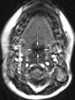

Enlarged adenoids

Adenoid hypertrophy (enlarged adenoids) is the unusual growth (hypertrophy) of the adenoid (pharyngeal tonsil) first described in 1868 by the Danish physician Wilhelm Meyer (1824–1895) in Copenhagen. He described a long term adenoid hypertrophy that will cause an obstruction of the nasal airways. [Source: Wikipedia ]